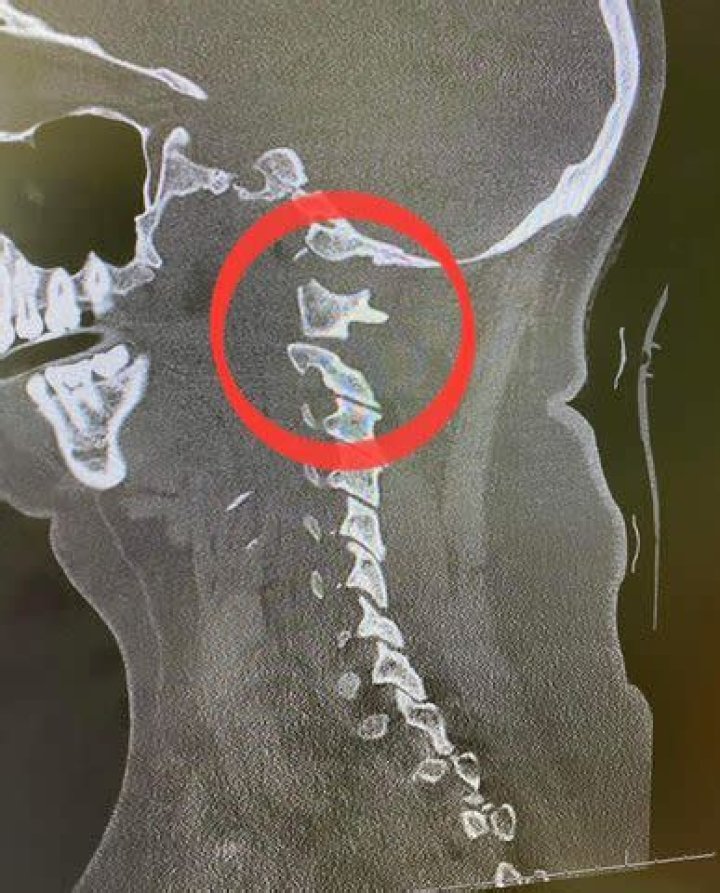

Man was internally decapitated CNN. Car wreck leaves child internally decapitated CNN Video. The tragic story of a dead baby shows the terrible toll of Ye...